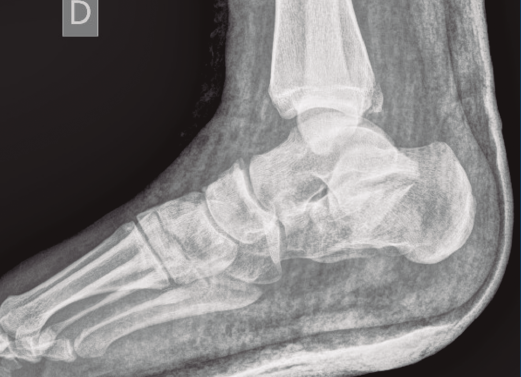

Figura 7. Radiografía lateral de pie y tobillo; se evidencia fractura de calcáneo y de maléolo tibial posterior.

A su llegada a urgencias, se inmovilizó con férula posterior de yeso tras no conseguirse la reducción cerrada (Figuras 7 y 8). Debido a la patología asociada, subsidiaria de tratamiento quirúrgico de urgencias (artrodesis de L2 a L4 con tornillos transpediculares, por parte de neurocirugía), se decide demorar eñ tratamiento definitivo de la fractura luxación de calcáneo 2 semanas, hasta conseguir una mejoría en el estado de las partes blandas.

Se trata de un varón de 19 años que ingresa en reanimación tras precipitarse desde una altura de aproximadamente 10 metros. El paciente presenta una fractura estallido de L3 con afectación del canal medular junto con una fractura del vértice inferior de L4, así como una fractura luxación de calcáneo, asociada a una fractura del maléolo peroneo y del maléolo tibial posterior (Figuras 1 a 6) diagnosticadas mediante TC total body (por eso no se dispone de radiografías simples al momento del ingreso). Como podemos comprobar, se trata de una fractura de doble trazo de tipo hundimiento/depresión de la carilla articular (Figuras 5 y 6).